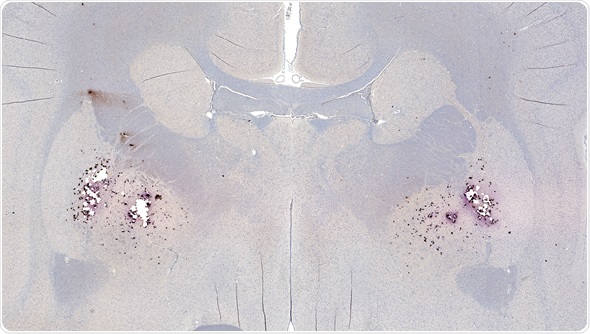

Image Copyright: vetpathologist, Image ID: 73918573 via www.shutterstock.com

Amyloid plaques consist of dense, mostly insoluble clumps in the spaces between the nerve cells in the brain tissue. The plaques are made up of beta-amyloid, which is a protein peptide or fragment that appears to have toxic effects on the function of the surrounding brain cells.

Over time, some individuals develop amyloid plaques in the central nervous system as they age. There are some regions of the brain that are particularly prone to the development of the plaques, such as in the hippocampus. The hippocampus is important for the processing of memories from short-term to long-term and damages in this area of the brain is associated with symptoms of Alzheimer’s disease.

The exact role of amyloid plaques in the pathogenesis of Alzheimer’s disease is not well understood. It is evident that they are more prevalent in individuals with the disease, but it is unclear if they cause or are a by-product of the disease. However, there is some evidence to support the suggestion that some genetic mutations lead to an increase in beta-amyloid production, responsible for causing some forms of Alzheimer’s disease.